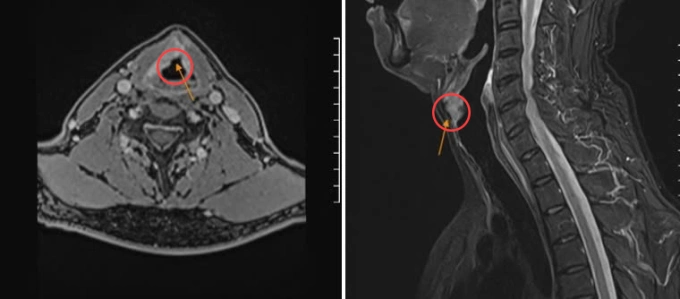

Kết quả nội soi họng thanh quản, chụp MRI tại Bệnh viện Đa khoa Tâm Anh TP HCM cho thấy hai dây thanh của ông Sang sung huyết, khối u sùi ở dây thanh môn mép trước, kích thước 20x18x14 mm và một số hạch cổ đường kính lớn nhất 6 mm. Sinh thiết khối u cho kết quả ung thư thanh quản dạng biểu mô tế bào vảy.

GS.TS.BS Trần Phan Chung Thủy, Giám đốc Trung tâm Tai Mũi Họng, Bệnh viện Đa khoa Tâm Anh TP HCM, cho biết tổn thương (u ác tính) đã lan vào sụn giáp bên phải nhưng chưa di căn hạch.

Chụp MRI ghi nhận khối u dây thanh phải xâm lấn sụn giáp. Ảnh: Bệnh viện Đa khoa Tâm Anh